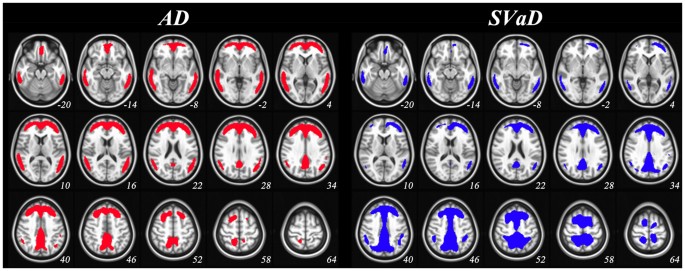

Figure 1 shows disease-specific CTX ROIs representing large differences in group-averaged PiB images between OC and patients (see the section of “Disease-specific CTX ROI”). SUVr of every voxel in the ROIs is significantly higher in patients (see Supplementary Fig. S1). Both CTXAD and CTXSVaD were mostly located in frontal, temporal and parietal regions. When evaluating proportions by lobe, CTXSVaD showed relatively larger proportions in parietal and lower proportions in temporal regions than CTXAD (Table 2).

Disease-specific cortical target regions. AD: Alzheimer’s disease; SVaD: subcortical vascular dementia. Colored areas indicate voxels by percent threshold (upper 3% intensity) of group-averaged difference between old control and patient groups, which was defined as disease-specific cortical target regions. The regions are mapped on MNI 152 template with the coordinates of the z-axis (numbers under each slice) to the MNI space.

In Klunk et al.1, the CTX ROI was defined using a data-driven mask thresholded at 1.05 SUVr (using the WC reference ROI) difference between group-averaged PiB images of 19 AD subjects and 25 age-matched older controls. The threshold was designed to avoid WM regions and to minimize the number of separate clusters in the CTX ROI, and small holes and isolated voxels were manually edited. Although the typical amyloid binding regions reported in previous studies were included in the published CTX ROI, there were two reasons to generate a new CTX ROI. First, the published CTX ROI was designed specifically for AD patients, and given different progression patterns between SVaD and AD26, it was reasonable to make a new CTX ROI for SVaD patients. The second reason necessitating a new CTX ROI was the use of a numerical SUVr threshold. While amyloid deposition was well represented using a CTX ROI 1.05 SUVr unit difference in the dataset of Klunk et al.1, this value has not been validated in other datasets. CTX ROI values may be highly variable across cohorts, especially in AD patients with lower severity. Therefore, new CTX ROIs for SVaD and AD patients (CTXAD and CTXSVaD ROIs) were generated (using WC as reference) using data from the 57 PiB (+) AD and 23 PiB (+) SVaD patients, as well as control data from the Alzheimer’s Disease Neuroimaging Initiative (ADNI). When creating disease-specific CTX ROIs, we compared disease group and 14 PiB (−) OC subjects to find regions of high amyloid accumulation in elderly. As described above, individual images were transformed to MNI-152 template space and SUVr values derived. The average OC image was (separately) subtracted from averaged AD and SVaD images and spatially smoothed with a 5 mm full width at half maximum kernel. To extract CTXAD and CTXSVaD ROIs, we applied a percent threshold (upper 3% intensity) to smoothed images to retain a similar number of voxels as the published CTX ROI1. These disease-specific CTX ROIs are shown in Fig. 1.